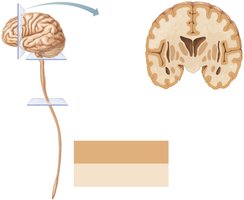

Organization of Gray and White Matter

Distribution Patterns

The CNS displays characteristic patterns of gray matter (neuron cell bodies, dendrites, glial cells) and white matter (myelinated axons):

In the spinal cord: central gray matter surrounded by white matter.

In the brain stem: additional gray matter nuclei embedded within white matter.

In the cerebrum and cerebellum: outer cortex of gray matter, inner white matter, and deep gray matter nuclei.